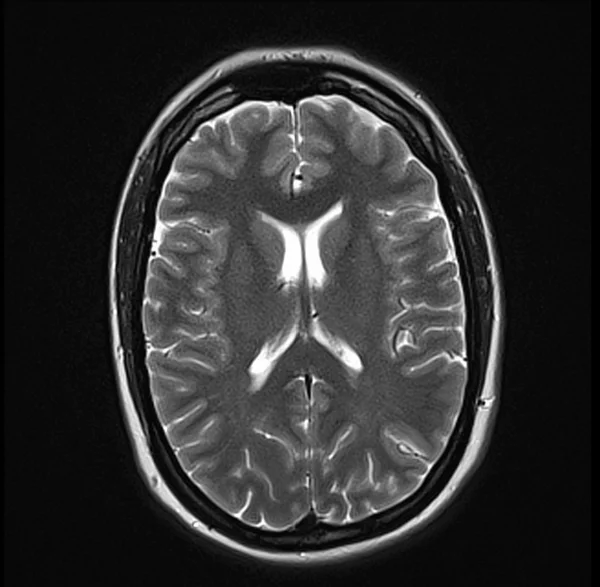

Brain MRI T2 axial images